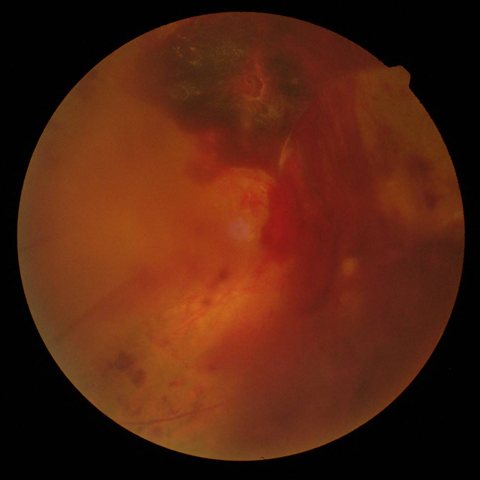

2.前増殖糖尿病網膜症

| 病期 | 症状 | 治療法 |

|---|---|---|

| 中期の網膜症 | 毛細血管がつまり血管閉塞を生じます。血管閉塞した網膜は虚血におちいり、軟性白斑という所見が生じます。 | 虚血網膜は放置することによって、新生血管が生じ、硝子体出血や増殖膜のもとになるため、この段階で、的確なレーザー治療(網膜光凝固術)をしっかりと行っておくことが非常に重要になります。 |

軟性白斑 |

レーザー光凝固施行前の糖尿病網膜症  レーザー光凝固施行後の糖尿病網膜症 |